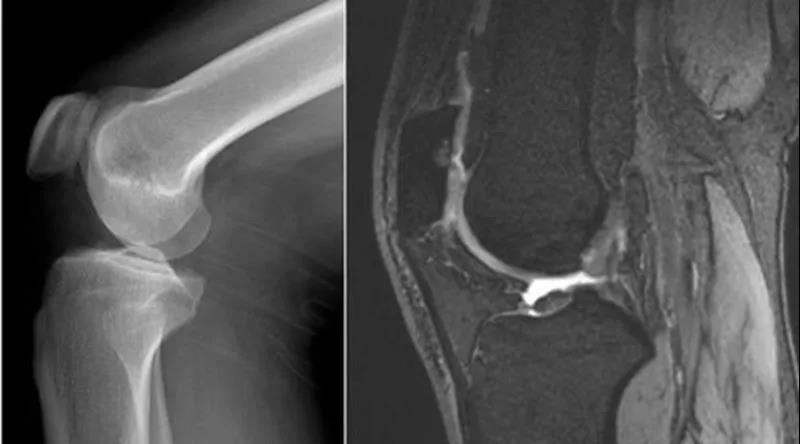

膝关节穿刺术常用于检查关节腔内积液的性质,或抽液后向关节腔内注药。膝关节腔内积液,需行关节穿刺抽液检查或引流,或注射药物进行治疗。关节腔内注射空气或造影剂,行关节造影术,以了解关节软骨或骨端的变化。

1、受伤(与运动有关)膝关节扭伤、半月板损伤、侧副韧带或交叉韧带损伤。2、感染(结核)。3、类风湿性关节炎、滑膜炎。

当关节退变、运动过力或创伤,使得关节腔内乳酸、组胺、缓激肽、前列腺素和神经肽等被激活,能够引起疼痛,同时膝关节腔内出现大量关节腔积液,压力增加,膝关节肿胀。